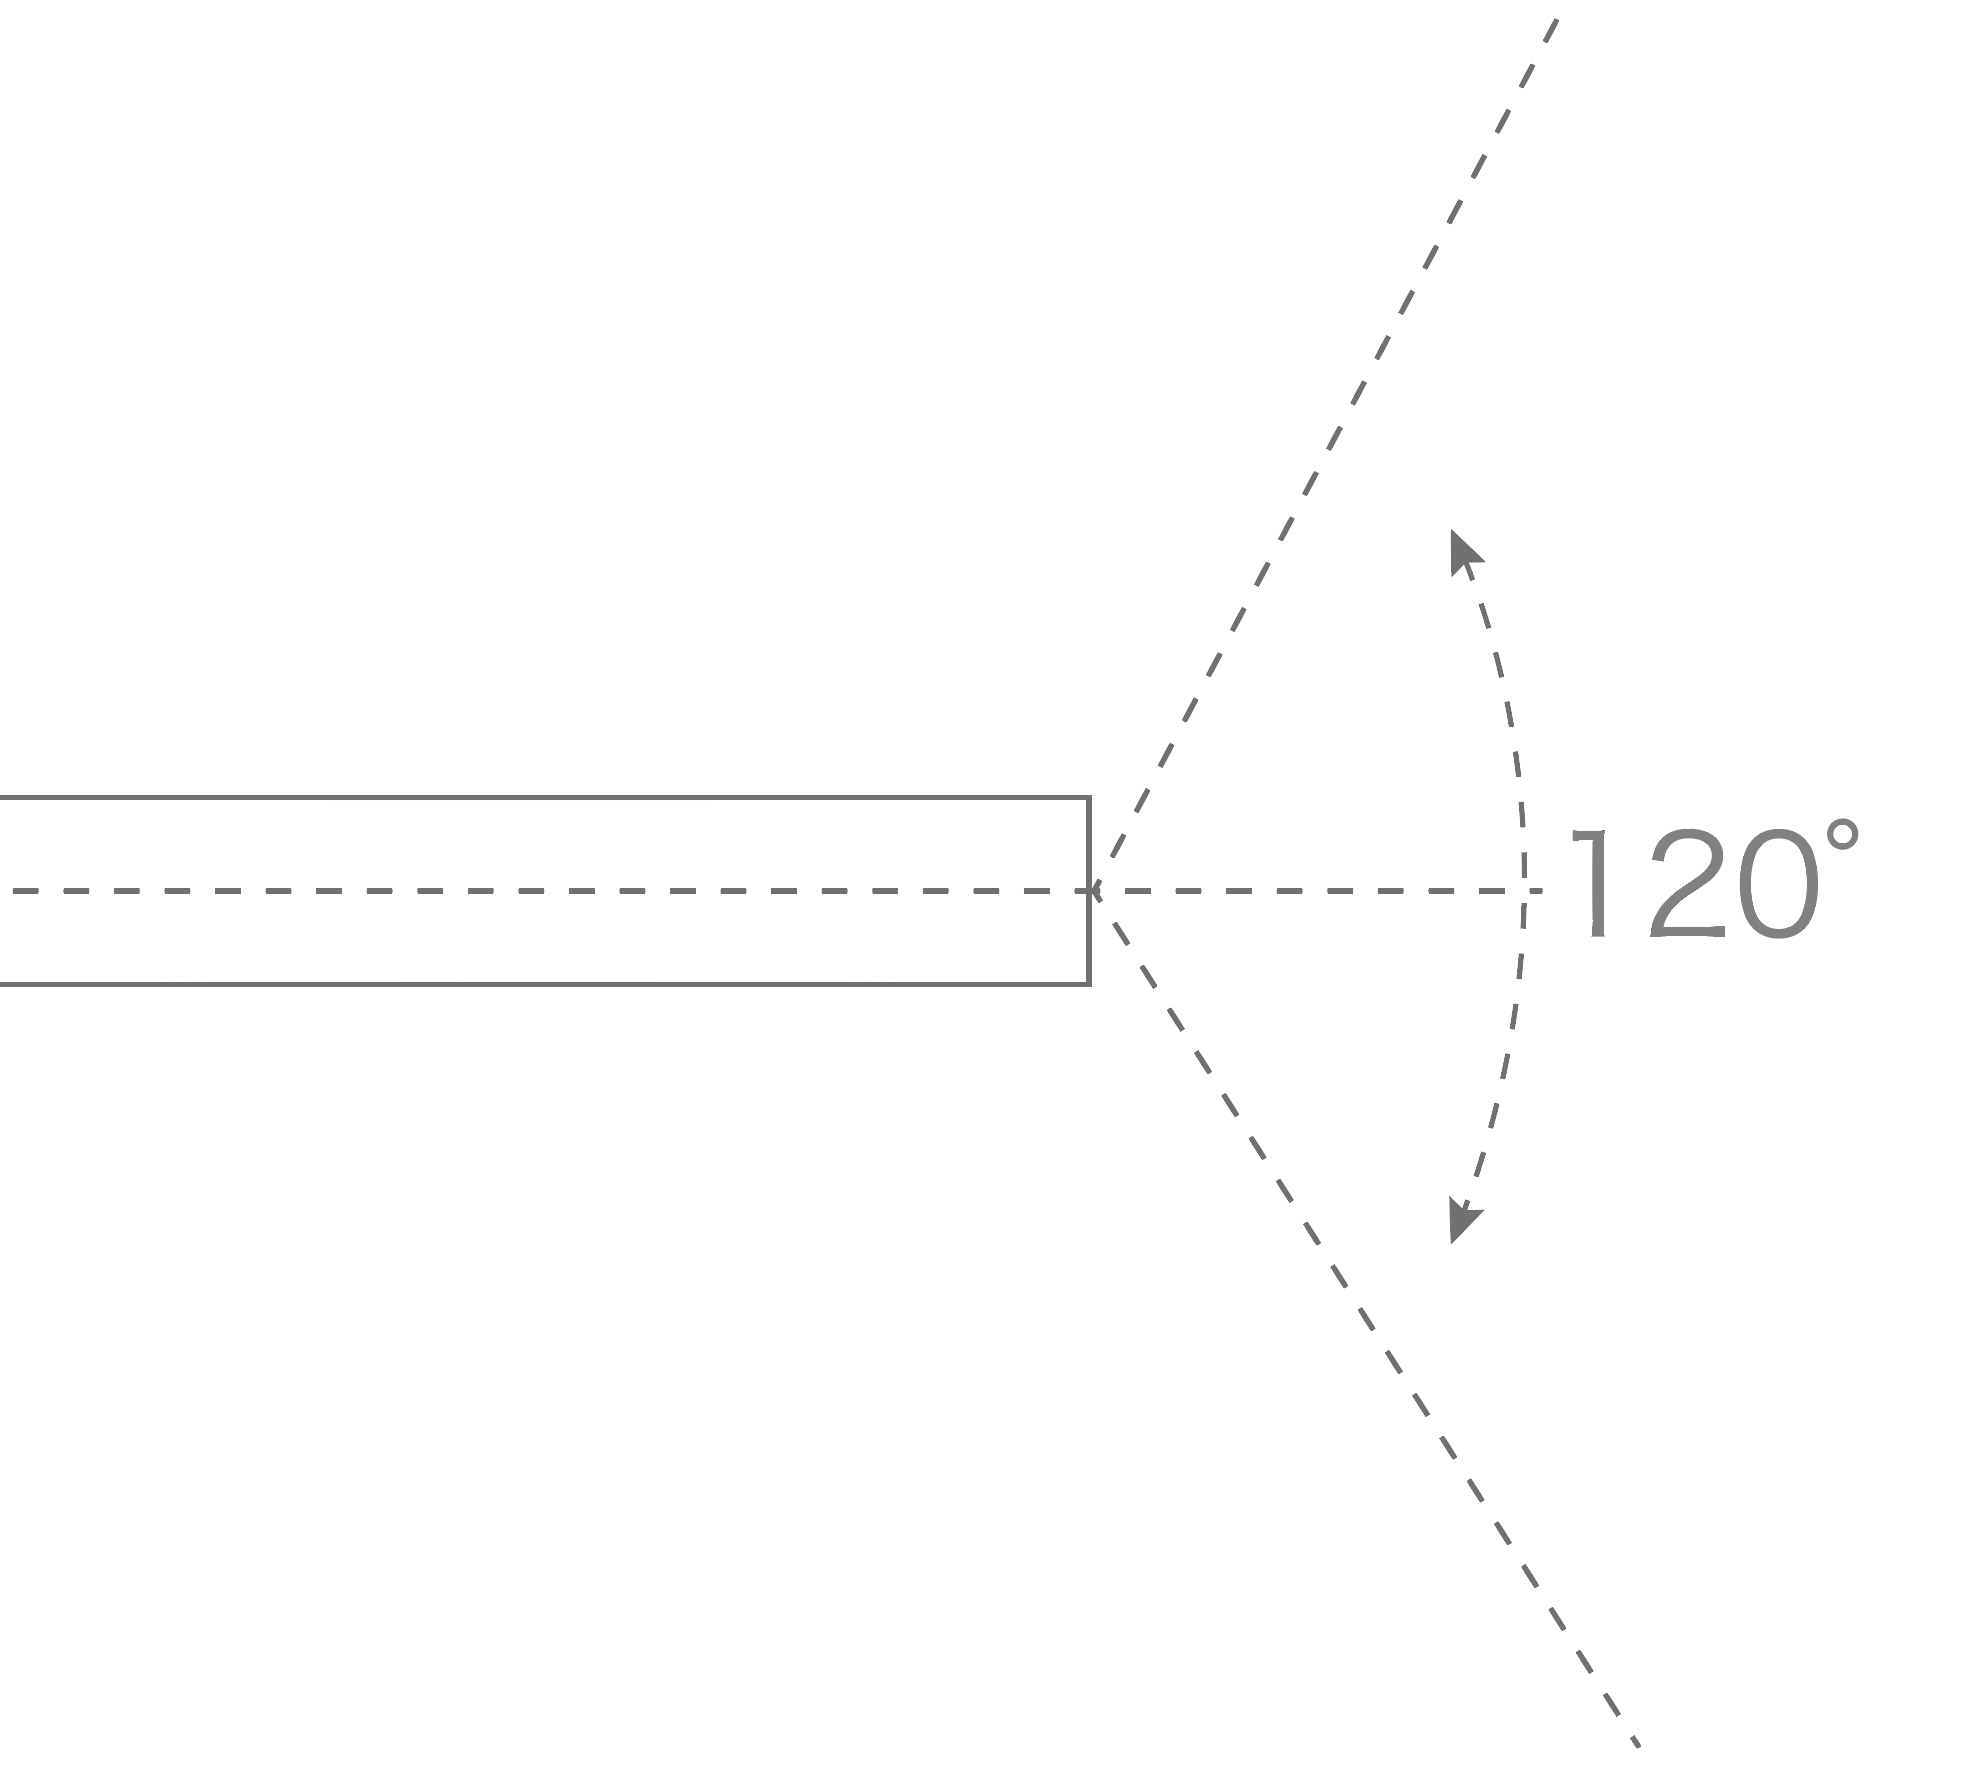

120°视场角,满足更大视野范围的观察。配合 VIST 染色,助力呼吸系统疾病的诊断。